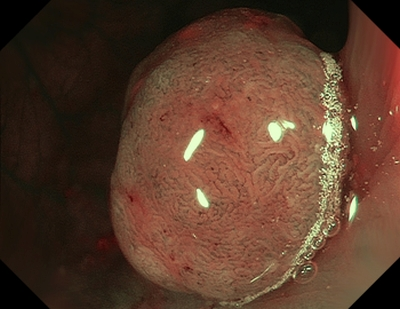

Тип 3 — характерний для злоякісної пухлини (ЗМ)

Колір: темніший за навколишнє, коричневий, іноді зі світлішими плямами

Судини: ділянки з перерваними або відсутніми судинами

Поверхня: аморфна або без малюнка на поверхні